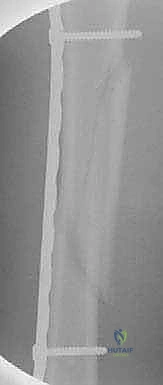

TECH FIG 4 • H,I. Postoperative AP radiographs of the long oblique proximal-third femur fracture managed with the submuscular plate.